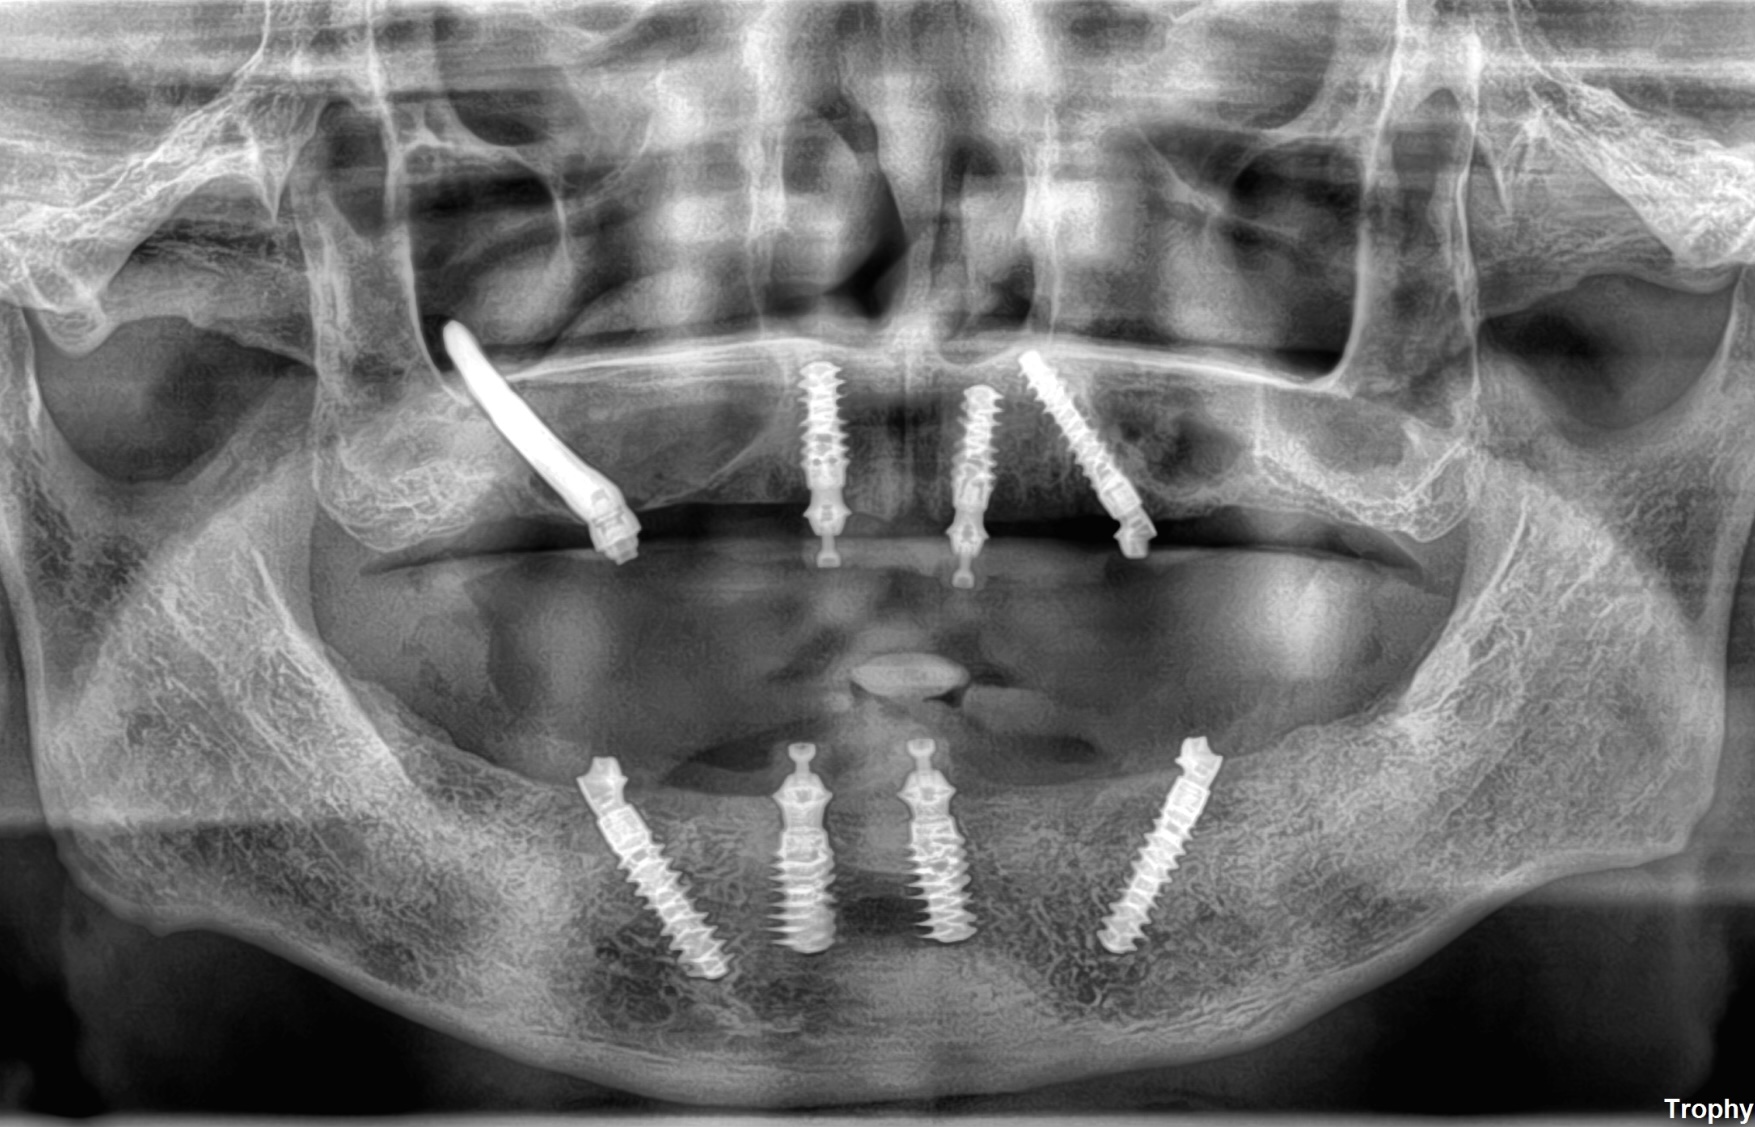

オールオン4allon4

ザイゴマインプラントzygoma

症例case